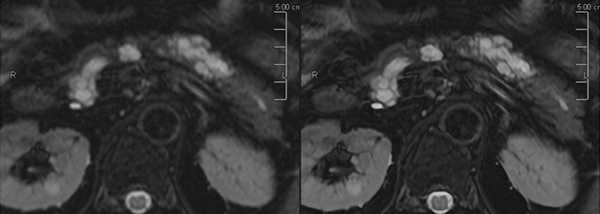

前田医師は、Vantage Centurianで撮像した転移性肝腫瘍の症例(図1)について、「臨床稼働後、最初期に撮像した画像でしたが、DWIで腫瘍が高信号に描出されるだけでなく、腫瘍中心部と辺縁部の信号のコントラストが鮮明に描出されており、Vantage Centurianの分解能の高さを実感しました」と述べる。また、膵臓の膵管内乳頭粘液性腫瘍(IPMN)の症例(図2)でも、PIQEを使用することで分解能が向上し従来画像よりも解像度が向上している。前田医師は、「PIQEの再構成画像では膵囊胞性病変の内部構造が非常にクリアになり、隔壁や充実成分のより詳細な評価が可能になるため、悪性度の評価が容易になります」と評価する。中村准教授はPIQEについて、「Vantage Centurianでは、基本画質の向上とPIQEによる再構成で、コントラストと分解能を両立した画像が得られています。画像の解像度が向上することで、病変の存在や悪性度などを悩まずに確信を持って読影することができます。不明瞭な画像では、ほかのシーケンスやモダリティの画像を確認することになるので、読影時間の短縮にもつながります」と述べる。

図2 IPMN(脂肪抑制T2WI 左:従来型再構成、右:PIQE再構成)